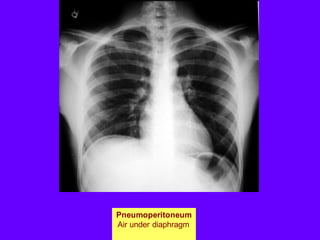

Pneumoperitoneum

Air under diaphragm

Elevated Diaphragm"

Note pneumoperitoneum

Supradiaphragmatic mass

Can be mistaken for elevated diaphragm